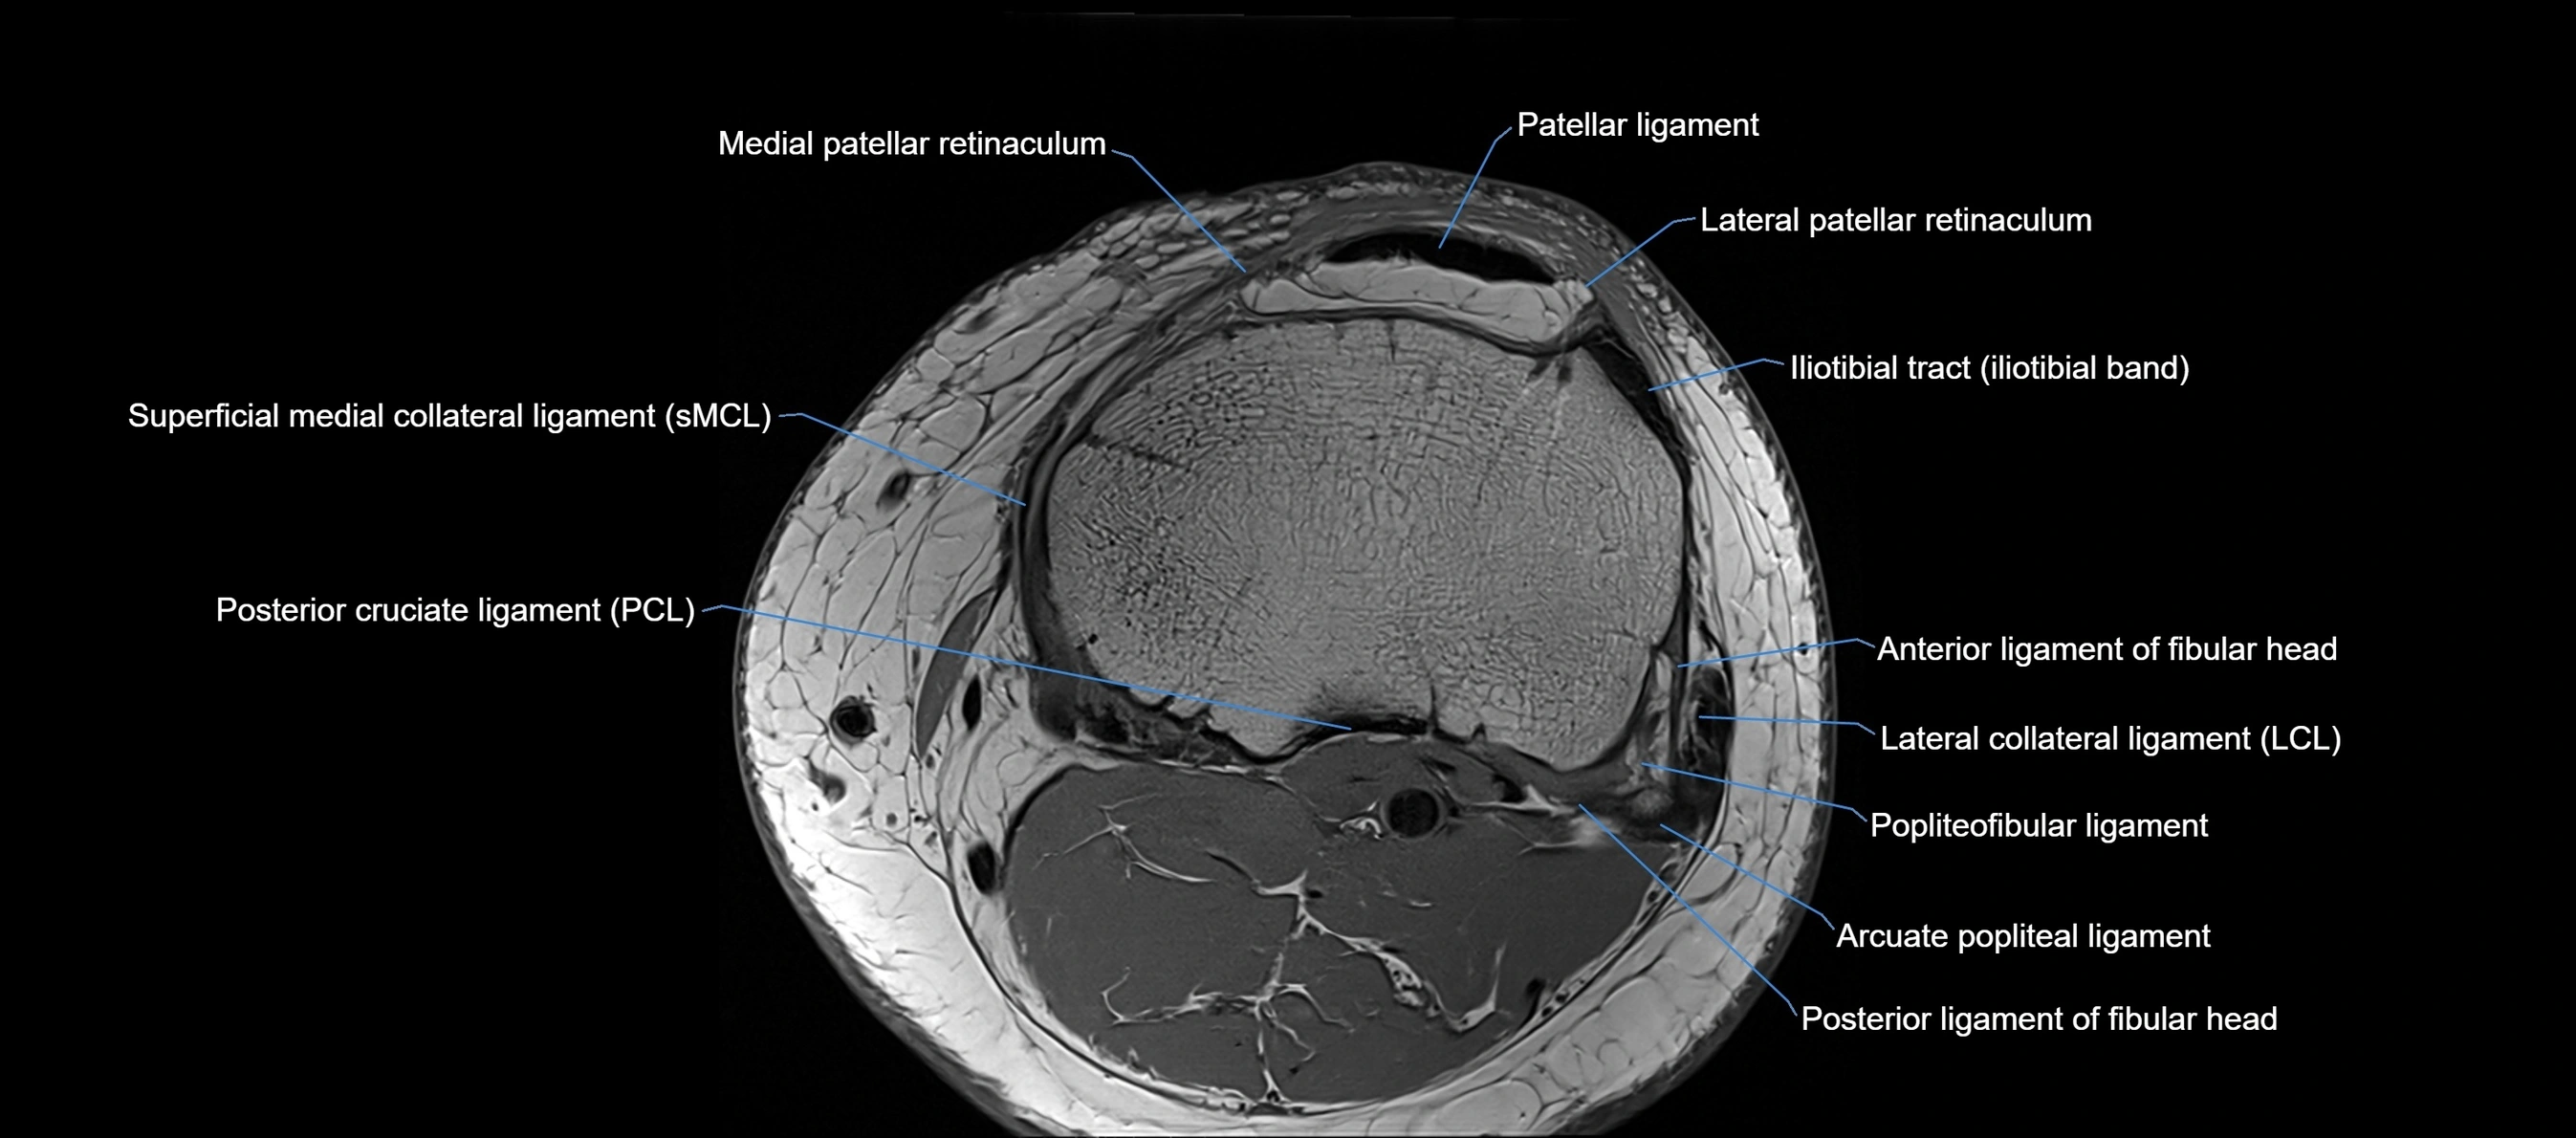

MRI images

image

MRI Appearance

T1-weighted images:

• Normal ACL appears as a low-signal band-like structure crossing the intercondylar notch

• Surrounded by intermediate signal synovial fluid and fat planes

T2-weighted images:

• Normal ACL remains low signal

• Partial or complete tears appear as discontinuity, increased signal, or fiber laxity